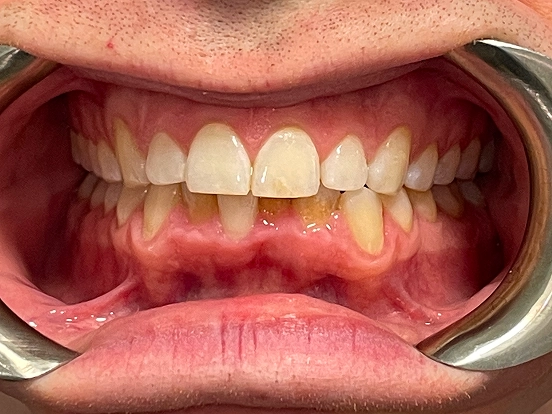

Braces GI

GI achieved a beautifully balanced smile through braces treatment. Over time, the brackets and wires gently moved each tooth into its ideal position, resulting in improved alignment, comfort, and confidence in their everyday smile.